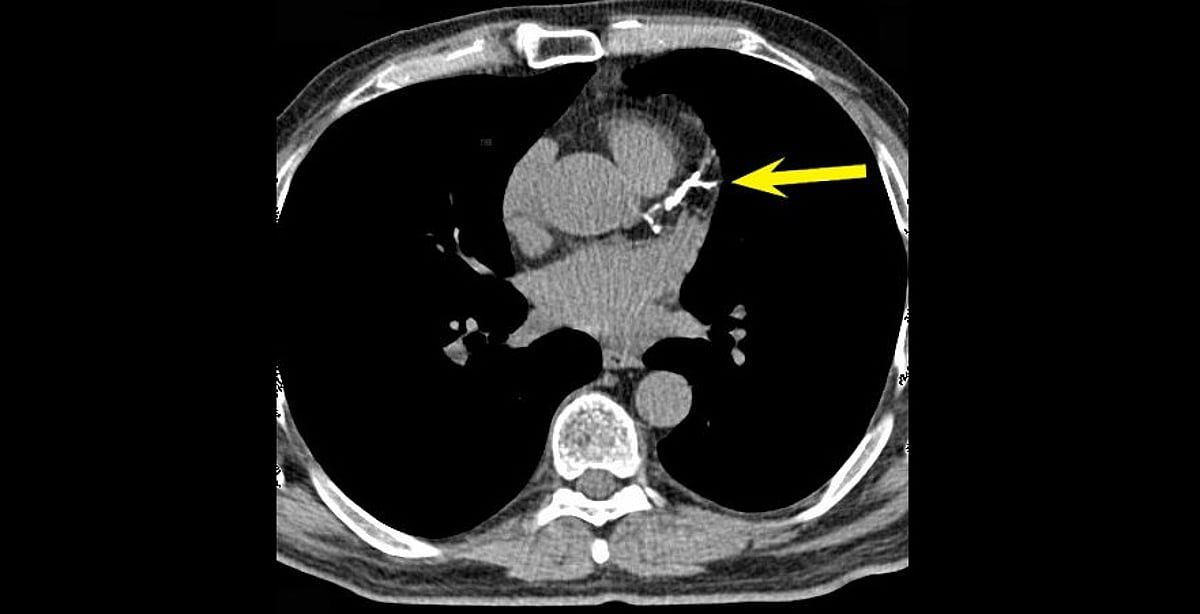

في توضيح طبي، أشار استشاري أمراض القلب الدكتور خالد النمر، إلى أن رقم تكلّس الشرايين (Calcium Score) غالبًا ما يرتفع تدريجيًّا مع التقدم في العمر، ووجود عوامل مثل ارتفاع ضغط الدم والسكري والتدخين، مؤكدًا أن الزيادة البسيطة لا تعني بالضرورة تدهور الحالة الصحية.

وضرب "النمر" مثالًا بأن من كان لديه رقم تكلّس 30 وأصبح 52 بعد 4 سنوات، فإن هذه الزيادة تُعد طبيعية ومتوقعة، إذ إن المعدل السنوي المقبول عادة لا يتجاوز 20 إلى 25٪.

وشدد على أهمية السيطرة على العوامل المسببة مثل الضغط، والكوليسترول، والتدخين، والوزن، حتى لا تتسارع نسبة التكلّس وتؤثر على صحة الشرايين.

وفيما يخص الوقاية، نصح "النمر" باستخدام الأسبرين للوقاية الأولية لمن لديهم تكلّس في الشرايين التاجية بشرط توفّر ثلاثة عوامل مجتمعة، هي:

* أن يكون رقم التكلّس أعلى من 100.

* أن تتجاوز قيمة معادلة ASCVD نسبة 5٪ خلال 10 سنوات.

* أن تكون مخاطر النزيف الناتجة عن استخدام الأسبرين منخفضة.